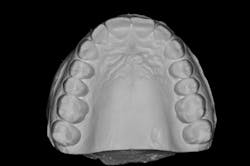

We always complete treatment on our models before we ever begin treatment on our patients, so that we are confident we can achieve the same result in the mouth. Below you will see that we completed a minimal wax-up to recontour the gingival levels and correct proportions and contours. We also worked out Dawson’s 5 requirements of occlusal stability by utilizing equilibration and refining the anterior guidance with our proposed restorations.

These models (figures 7–10) can then be sent to the laboratory for fabrication of the final wax-up, reduction guides, and provisional matrices. In contrast, we could also scan these models and upload the files to perfect our digital wax-up.